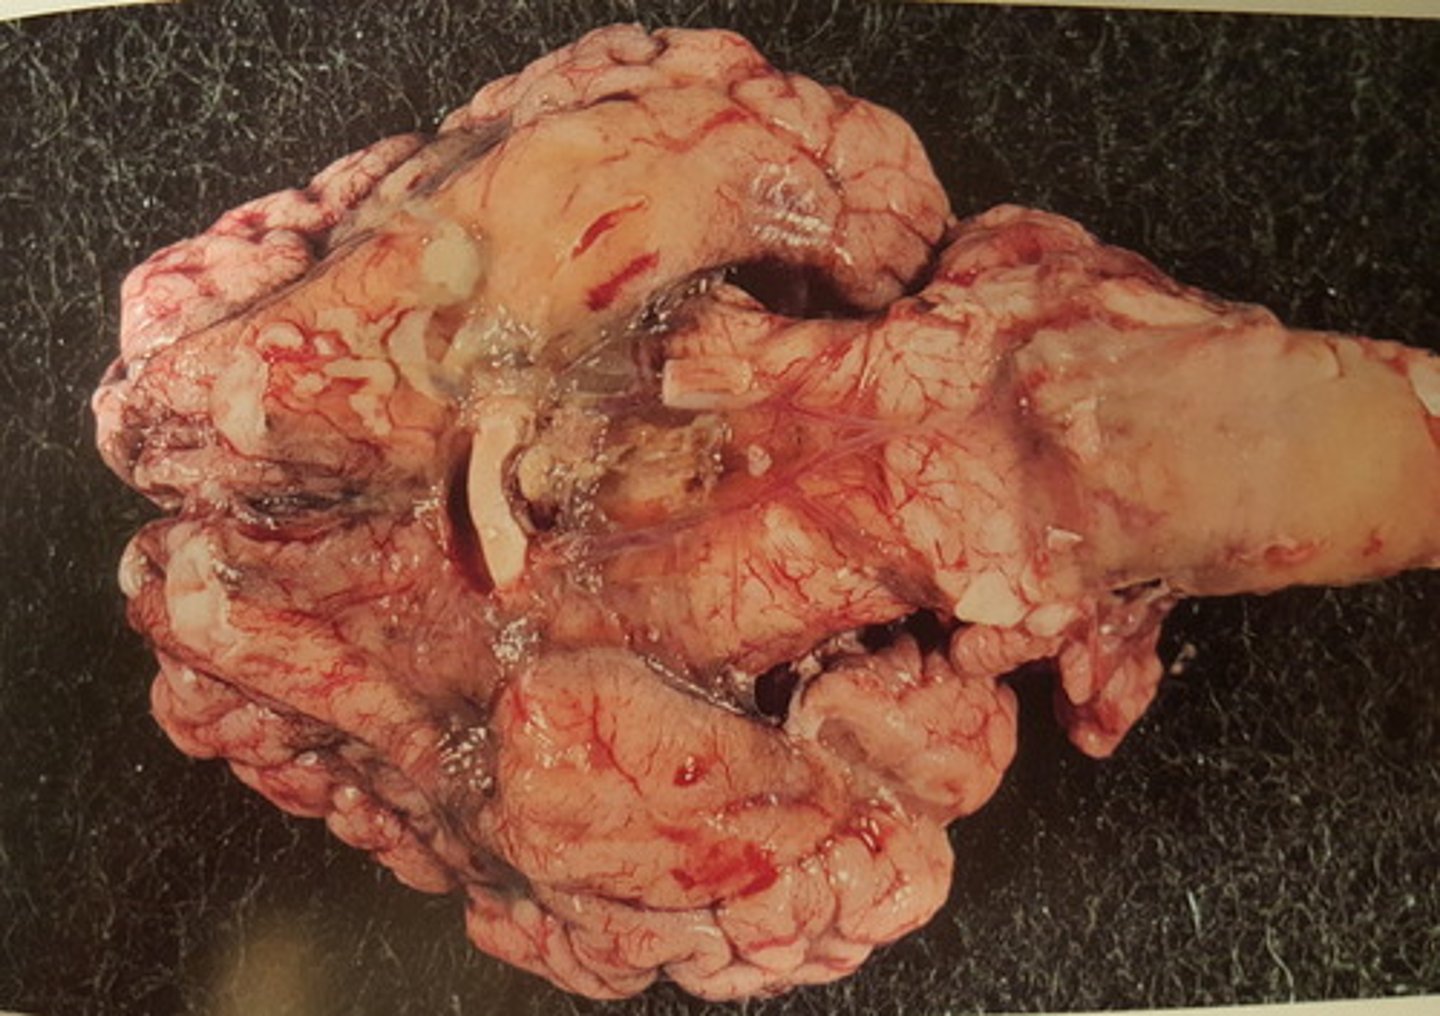

kronisk dissemineret granulomatøs meningitis Infektion med mycobacterium bovis

Rygmarv med hinder fra okse. Patoanatomisk diagnose? Ætiologi?

kronisk dissemineret granulomatøs encephalitis og meningitis. Infektion med mycobacterium bovis

Hjerne med hinde fra okse. Patoanatomisk diagnose? Ætiologi?